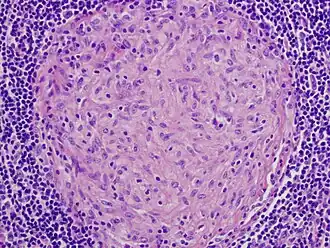

| Picture of a granuloma (without necrosis) as seen through a microscope on a glass slide: The tissue on the slide is stained with two standard dyes (hematoxylin: blue, eosin: pink) to make it visible. The granuloma in this picture was found in a lymph node of a patient with a Mycobacterium avium infection. | |

Macrophages (specifically histiocytes) are the cells that define a granuloma. They often fuse to form multinucleated giant cells (Langhans giant cell).[7] The macrophages in granulomas are often referred to as "epithelioid". This term refers to the vague resemblance of these macrophages to epithelial cells. Epithelioid macrophages differ from ordinary macrophages in that they have elongated nuclei that often resemble the sole of a slipper or shoe. They also have larger nuclei than ordinary macrophages, and their cytoplasm is typically pinker when stained with eosin. These changes are thought to be a consequence of "activation" of the macrophage by the offending antigen.

The other key term in the above definition is the word "organized" which refers to a tight, ball-like formation. The macrophages in these formations are typically so tightly clustered that the borders of individual cells are difficult to appreciate. Loosely dispersed macrophages are not considered to be granulomas.